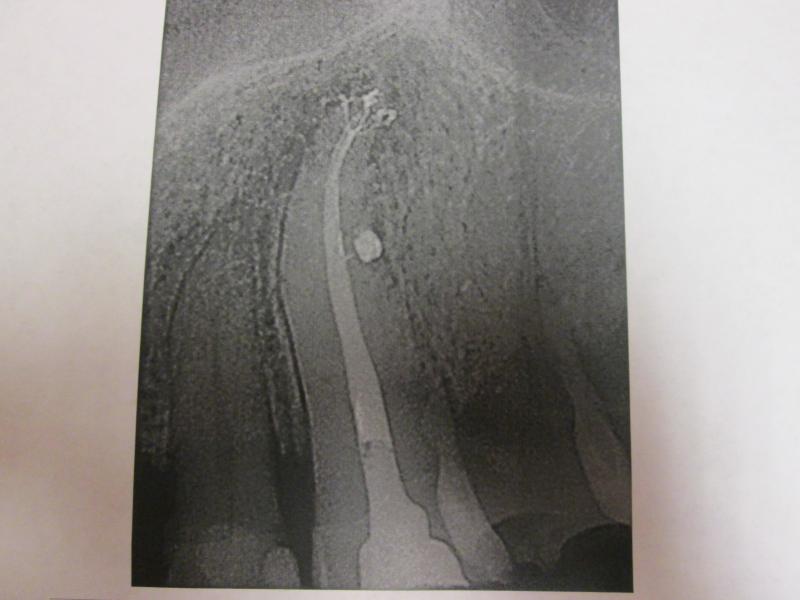

"DR. JET'S MISSION IS TO PERFORM  ROOT CANALS FOR A REDUCED FEE USING THE LATEST TECHNOLOGY  AND TECHNIQUES TO SERVICE THE MANY PEOPLE WHO ARE UNINSURED OR UNDER-INSURED GIVING EVERYONE AN OPPORTUNITY TO SAVE THEIR TOOTH!"

**PLEASE BE AWARE THAT  A ROOT CANAL IS AN ATTEMPT TO SAVE YOUR ALREADY DAMAGED TOOTH.  THERE IS NO GUARANTEE THAT ANY TOOTH CAN BE SAVED BUT DR JET WILL DO HIS BEST TO HELP YOU. THE OTHER OPTION IS TO EXTRACT YOUR TOOTH